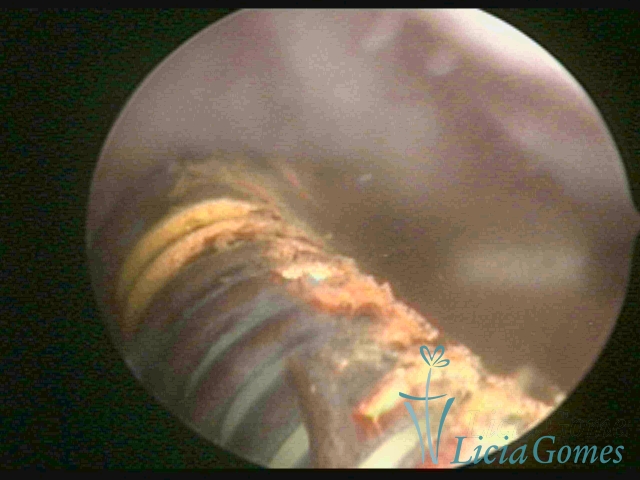

Uterine cavity with Mirena® endoceptive wrapped in a purulent secretion